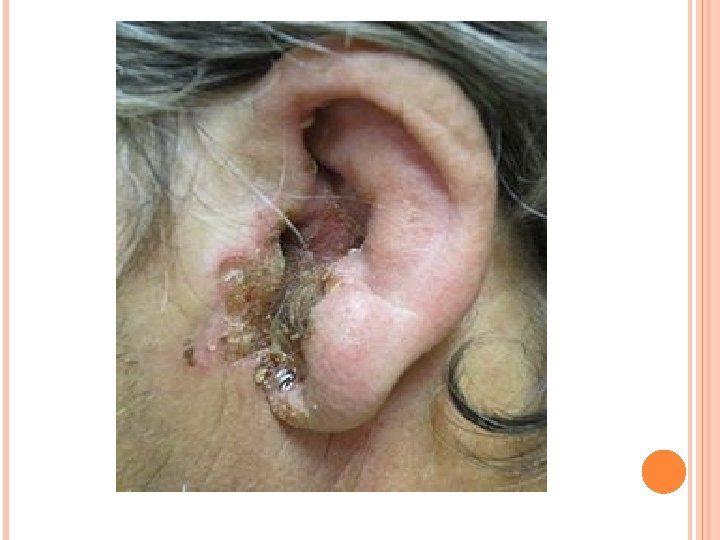

Otitis externa maligna (Pseudomona) Esta infección consiste en una infección del oído externo producida por Pseudomona aeruginosa, que se extiende a los tejidos blandos adyacentes al temporal y ocasiona osteomielitis de la base del cráneo, y puede producir afectación de pares craneales y complicaciones a nivel endocraneal. Suele producirse en pacientes inmunodeprimidos y diabéticos y es grave. Los síntomas iniciales son los mismos que los de una otitis externa difusa, después se acentúa el dolor y la otorrea, siendo mayores que los de una otitis externa convencional. Por otoscopia vemos un CAE edematoso, doloroso al tacto, con una secreción espesa verdosa, además podemos ver en el suelo del CAE unas granulaciones y áreas ulceradas. Si sigue progresando puede haber parálisis facial y afectación de pares craneales bajos. El tratamiento requiere ingreso hospitalario y administración endovenosa de ciprofloxacino. Además se realiza un tratamiento local del oído externo con ciprofloxacino tópico y limpieza exhaustiva. El pronóstico es grave debe saltar la alarma en un paciente anciano, diabético o inmunodeprimido, con una otitis externa que evoluciona mal.